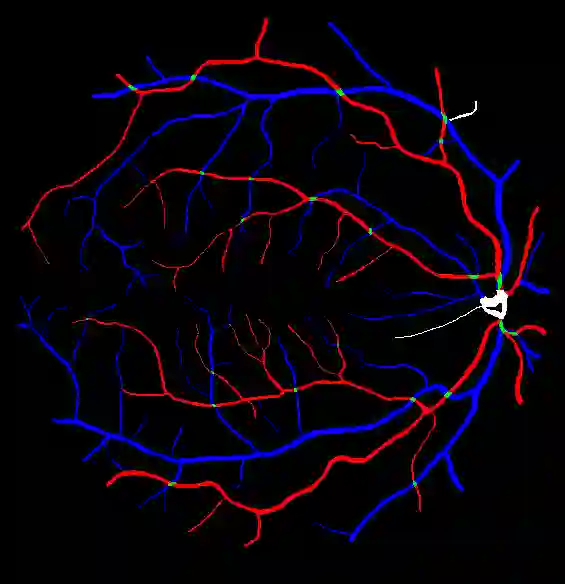

Retinal artery/vein (A/V) classification is a critical technique for diagnosing diabetes and cardiovascular diseases. Although deep learning based methods achieve impressive results in A/V classification, their performances usually degrade severely when being directly applied to another database, due to the domain shift, e.g., caused by the variations in imaging protocols. In this paper, we propose a novel vessel-mixing based consistency regularization framework, for cross-domain learning in retinal A/V classification. Specially, to alleviate the severe bias to source domain, based on the label smooth prior, the model is regularized to give consistent predictions for unlabeled target-domain inputs that are under perturbation. This consistency regularization implicitly introduces a mechanism where the model and the perturbation is opponent to each other, where the model is pushed to be robust enough to cope with the perturbation. Thus, we investigate a more difficult opponent to further inspire the robustness of model, in the scenario of retinal A/V, called vessel-mixing perturbation. Specially, it effectively disturbs the fundus images especially the vessel structures by mixing two images regionally. We conduct extensive experiments on cross-domain A/V classification using four public datasets, which are collected by diverse institutions and imaging devices. The results demonstrate that our method achieves the state-of-the-art cross-domain performance, which is also close to the upper bound obtained by fully supervised learning on target domain.